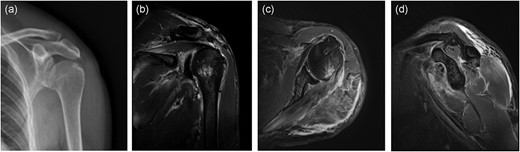

Left shoulder joint X-ray, three-dimensional CT (3D CT), and magnetic resonance imaging (MRI) were performed after admission. X-ray and 3D CT scanning revealed an upward shift of the left humeral head, fracture of the anterior inferior glenoid of the left shoulder, and Hill-Sachs injury of the posterolateral left humeral head (Fig. 2a–c). MRI scanning revealed the left humeral head moved up obviously and the subacromial space of the shoulder decreased. The distance between the acromion and humeral head was about 4 cm. The supraspinatus tendon retracted ~4 cm, and the anterior and posterior lacerations were ~4 cm in size. The involved tendons were supraspinatus, infraspinatus, and subscapular, but were not accompanied by significant muscle atrophy and fat infiltration (Fig. 2d–f).

Preoperative imaging: (a) anteroposterior X-ray of the left shoulder; (b) anteroposterior CT 3D reconstruction of the left shoulder; (c) coronal CT radiograph of the left shoulder; (d) anteroposterior MRI of the left shoulder; (e) coronal MRI of the left shoulder; (f) sagittal MRI of the left shoulder.